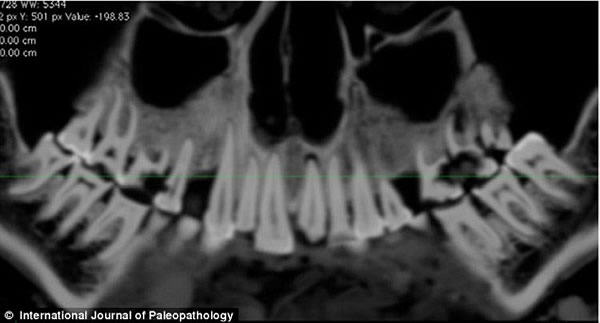

上图是木乃伊口腔CT扫描图,可以看到亚麻布团被填充在右部。

《古病理学国际期刊》的文章称,来自加拿大西安大略大学的安德鲁·韦德利用一种新型高分辨率CT仪扫描木乃伊的牙齿和身体,并且根据扫描片重建了3D图以进行更为细致的研究。从CT扫描片可以看到,木乃伊的一颗牙齿龋洞里塞着一块亚麻布团。这块亚麻布之前可能经过无花果汁液或雪松油等药物的浸泡,随后被塞入下颚第一、二颗臼齿中间,也就是最大、也是最疼的龋洞里。这么做既能起到抵挡食物残渣进入龋洞的屏障作用,又能利用亚麻布上的药物缓解疼痛。